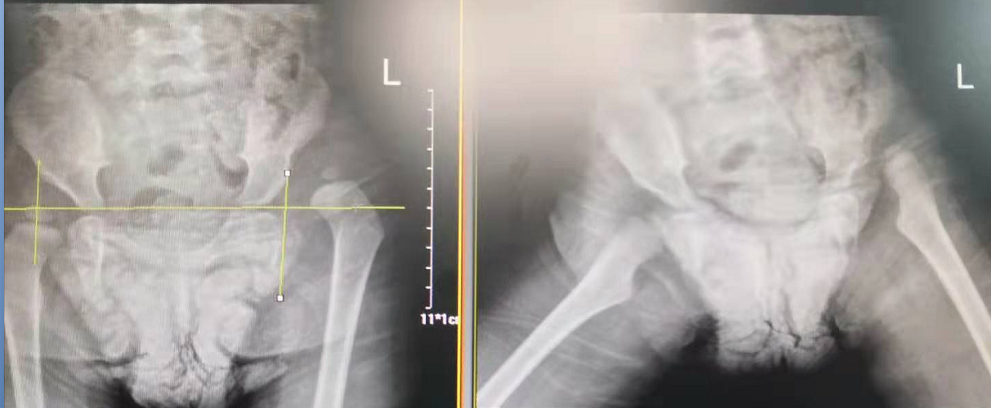

術(shù)前

術(shù)后

據(jù)了解,玥玥的左腿比右腿要短3厘米,導(dǎo)致她走起路來“不對頭”:一拐一拐的,像小鴨子走路一樣。